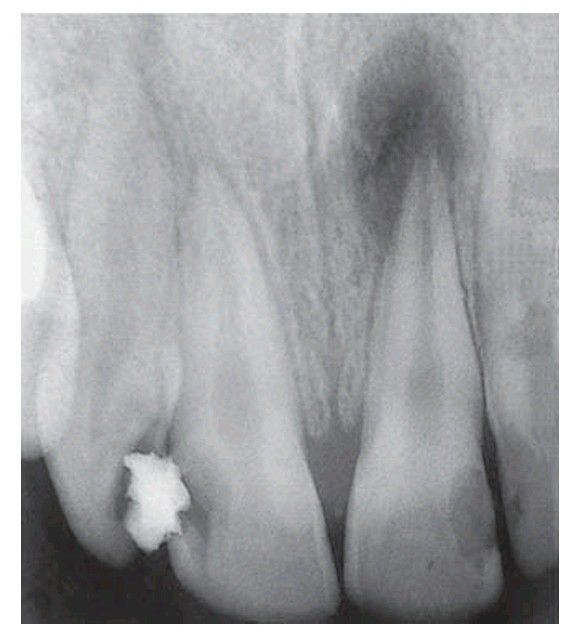

Chronic apical abscess

. Periapical bone resorption has developed as a result of infl ammation. The area of radiolucency corresponds with the histological changes.